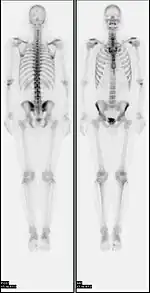

![]() A nuclear medicine whole-body bone scan. The nuclear medicine whole-body bone scan is generally used in evaluations of various bone-related pathology, such as for bone pain, stress fracture, nonmalignant bone lesions, bone infections, or the spread of cancer to the bone. | |

A bone scan or bone scintigraphy /sɪnˈtɪɡrəfi/ is a nuclear medicine imaging technique of the bone. It can help diagnose a number of bone conditions, including cancer of the bone or metastasis, location of bone inflammation and fractures (that may not be visible in traditional X-ray images), and bone infection (osteomyelitis).[1]

Nuclear medicine provides functional imaging and allows visualisation of bone metabolism or bone remodeling, which most other imaging techniques (such as X-ray computed tomography, CT) cannot.[2][3] Bone scintigraphy competes with positron emission tomography (PET) for imaging of abnormal metabolism in bones, but is considerably less expensive.[4] Bone scintigraphy has higher sensitivity but lower specificity than CT or MRI for diagnosis of scaphoid fractures following negative plain radiography.[5]

In a typical bone scan technique, the patient is injected (usually into a vein in the arm or hand, occasionally the foot) with up to 740 MBq of technetium-99m-MDP and then scanned with a gamma camera, which captures planar anterior and posterior or single photon emission computed tomography (SPECT) images.[19][14] In order to view small lesions SPECT imaging technique may be preferred over planar scintigraphy.[20]

In a single phase protocol (skeletal imaging alone), which will primarily highlight osteoblasts, images are usually acquired 2–5 hours after the injection (after four hours 50–60% of the activity will be fixed to bones).[19][14][21] A two or three phase protocol utilises additional scans at different points after the injection to obtain additional diagnostic information. A dynamic (i.e. multiple acquired frames) study immediately after the injection captures perfusion information.[21][22] A second phase "blood pool" image following the perfusion (if carried out in a three phase technique) can help to diagnose inflammatory conditions or problems of blood supply.[23]